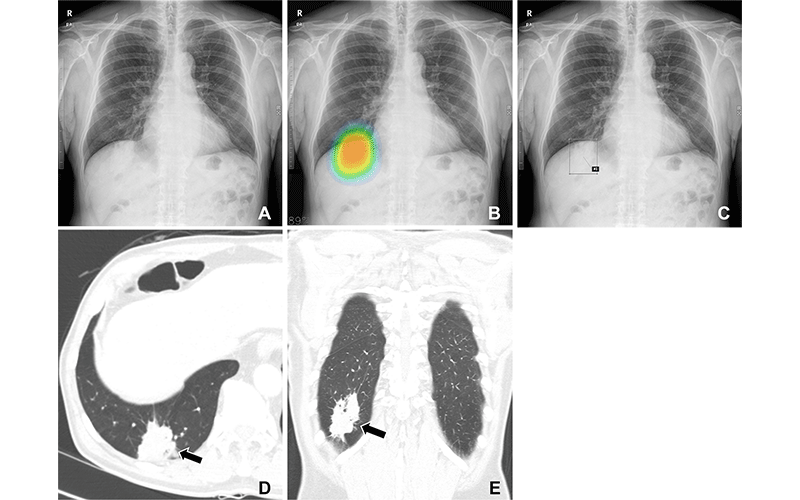

Head and neck cancers are a major concern in ENT. Early detection is critical for better survival rates. AI algorithms trained on thousands of images can now spot tiny, early-stage tumors on scans or endoscopic images. Studies have shown that some AI systems can match — or even surpass — human specialists in detecting certain cancers, like nasopharyngeal carcinoma. This does not replace doctors but acts as an extra pair of eyes that never gets tired.

2. Imaging and Radiology

AI is also revolutionizing ENT radiology. In CT and MRI scans of the sinuses or inner ear, AI can automatically detect anatomical variations, inflammation, or tumors. For cochlear implants, AI can help map the patient’s cochlear anatomy and suggest the best electrode placement for optimal hearing outcomes.